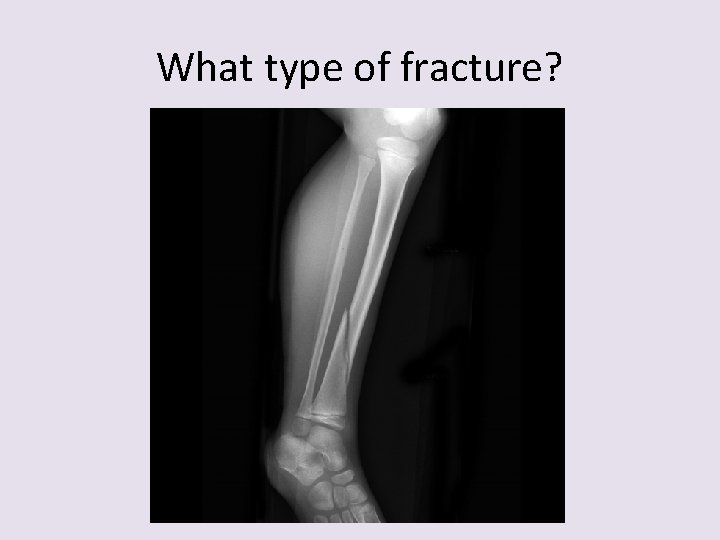

What type of fracture?